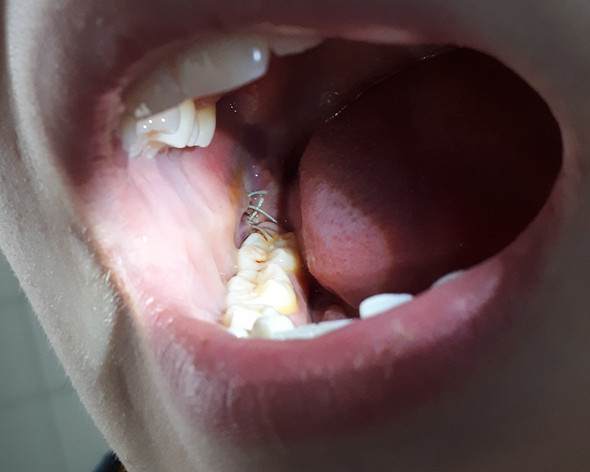

Aufgerissene Und Ungenahte Wunde Nach Weisheitszahn Op Schmerzen Blut Operation

Anlass war dass sich das Zahnfleisch über dem rechten Zahn entzündet hat und eiterte. Der Grund dafür ist zumeist dass das sogenannte Blutkoagulum ein Blutpfropfen der sich nach der OP an der betroffenen Stelle bildet zerfällt oder durch allzu starkes Gurgeln herausgespült. Solange die Wunde jedoch offen ist können Fremdkörper und Bakterien in die Wunde gelangen und so eine Entzündung auslösen. Grund dafür sind Bakterien die in die Wunde eindringen und das umliegende Gewebe ebenfalls befallen. Wenn allerdings zusätzlich plötzlich wieder zunehmender Schmerz Rötung und Temperaturanstieg hinzukommen sollte schnellstens der Zahnarzt aufgesucht werden. Weisheitszähne die nur teilweise durchgebrochen sind haben zudem eine Zahnfleischtasche als Überzug die sich entzünden kann. Dabei wird oft auch Eiter abgesondert. Ich war täglich beim Zahnarzt und habe mir den Streifen wechseln lassen und die Wunde wurde behandelt ausgekratzt neuer Medikamentenstreifen rein Das war höllisch schmerzhaft deswegen habe ich mir beim. Es ist schon mehr als ein Jahr nach meiner Weisheitszahn Op vergangen und ich musste heute leider feststellen dass Eiter aus der Wunde im Unterkiefer herauskommt.